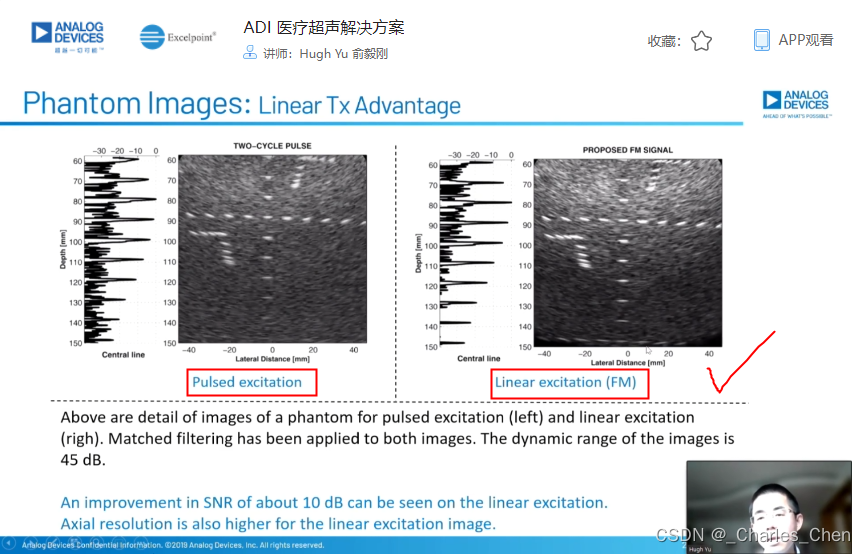

数字发射波束成形器用于产生所要求的数字发射信号,以正确的时间和相位生成聚焦发射信号。高性能超声系统可通过任意波形发生器产生复杂的发射波形,从而优化图像质量。这些情况下,发射波束成形器以大约40MHz速率生成8位至10位数字字符,并以此产生所要求的发射波形。数/模转换器(DAC)将数字波形转换成模拟信号,通过线性高压放大器进行放大,用于驱动传感器单元。由于这种发射技术占用较大体积,而且价格昂贵、需要消耗较高能量,所以,这种架构只限于昂贵的非便携设备。多数超声系统并不使用这种发射波束成形技术,而是采用多级高压脉冲发生器产生需要发射的信号。在这种替代方案中,利用高集成度、高压脉冲发生器快速切换传感器单元至适当的可编程高压电源,产生发射波形。为了产生一个简单的两极发射波形,脉冲发生器需要交替地将传感器单元切换到由数字波束成形器控制的正、负发射电压。更复杂的设计可以让传感器单元切换至多路电源和地,从而产生更复杂、性能更好的多重波形。